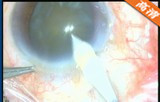

该手术在10点钟位透明角膜主切口制作,前房注入粘弹剂,2点钟位侧切口制作,撕囊镊做连续环形撕囊,做水分离和水分层 ,预吸晶状体皮质 ,超乳劈核法劈核,并逐块乳化吸除核块以及皮质,I/A吸除残留的皮质并对后囊膜进行抛光,前房及囊袋注入粘弹剂,植入爱尔康多焦人工晶状体,吸除前房以及人工晶状体后的粘弹剂。